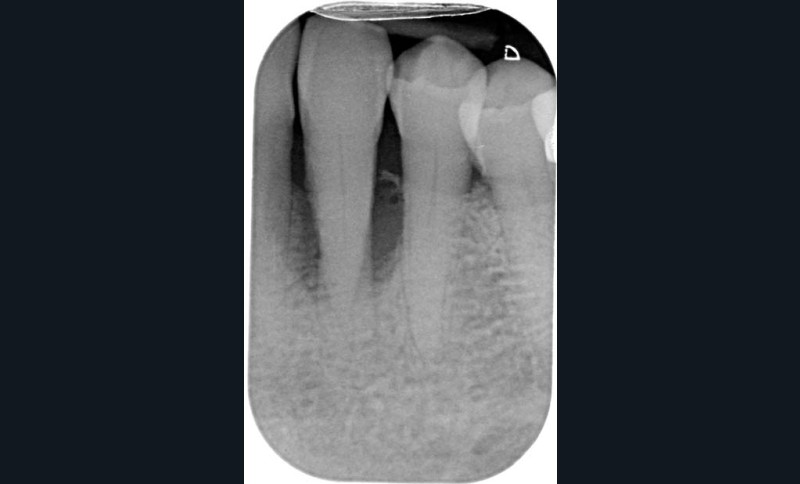

Le diagnostic différentiel avec la lésion d’origine endodontique et la lésion endo-parodontale devra s’appuyer sur le sondage, le test de vitalité et l’examen radiographique par radio rétro-alvéolaire. En cas de lésion d’origine parodontale, le sondage est arciforme, le test de vitalité est positif et une image radio-claire latérale peut être observée sur le cliché rétro-alvéolaire (tableau 1, fig. 2).